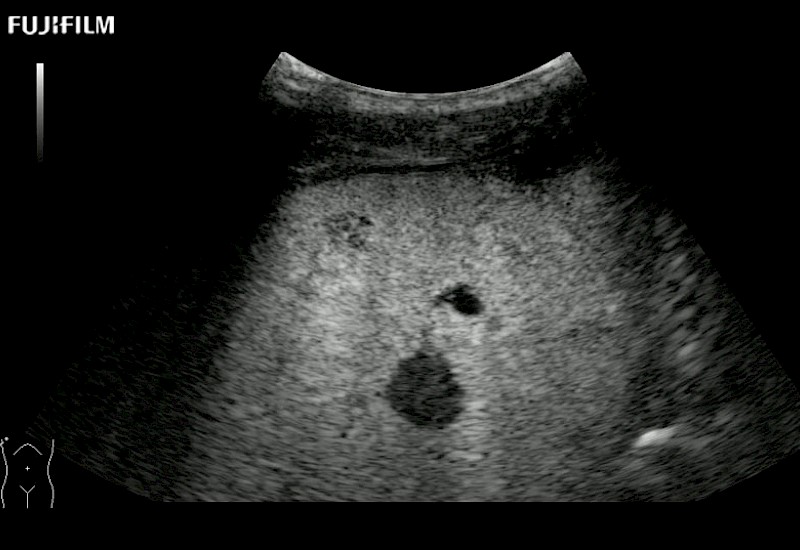

Our dedication to Laparoscopic Surgery allows us to offer superior image quality, outstanding system reliability and intuitive use of cutting edge technology.